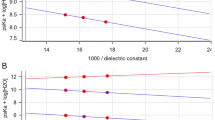

There was a linear correlation between CT number and both iodine concentration and bismuth bead volume/mL at each energy level (Fig. 5) of microsphere 6. For iodine, the largest difference in HU value was observed between 80 kVp and Sn150 kVp acquisitions, as compared to the 100 and Sn150 kVp. For bismuth, the HU difference was slightly more between 100 and Sn150 kVp; however, both acquisitions would be feasible to image bismuth with minimum HU differences.

The final material decomposition analysis was performed using the 80 kVp and Sn150 kVp paired acquisition, as the iodine extraction was favorable for this acquisition pair. There was a good linear correlation between the iodine concentration and dual energy index (DEI) (r2 = 0.9, p < 0.01), while there was a poor linear correlation between the bismuth volume and DEI (r2 = 0.34, p < 0.01) as shown in Fig. 6. The DEI threshold that optimally separated iodine and bismuth was defined at 0.06. 99.9% of the voxels in the 10 mg I/mL tubes were above this threshold, while 99.7% of the 62.5 mL/mL voxels in the bismuth agarose solution were excluded (Fig. 7). For the mixed tubes, the HU of all voxels were above the threshold (Supplementary Table 2).

Correlation of CT numbers (HU) on dual energy CT at 80 kVp vs Sn150 kVp: iodine, bismuth beads (6) and mixture of both. (A) Scatter plots of the CT numbers (HU) derived from the 80 kVp and Sn150 kVp scans for each voxel. Subplots are shown as (A1) iodine (red), (A2) bismuth (green), and (A3) a mixture of both (orange). (B) The average and standard deviation (bars) of the CT number (HU) derived from the 80 kVp and Sn150 kVp scans for each tube.